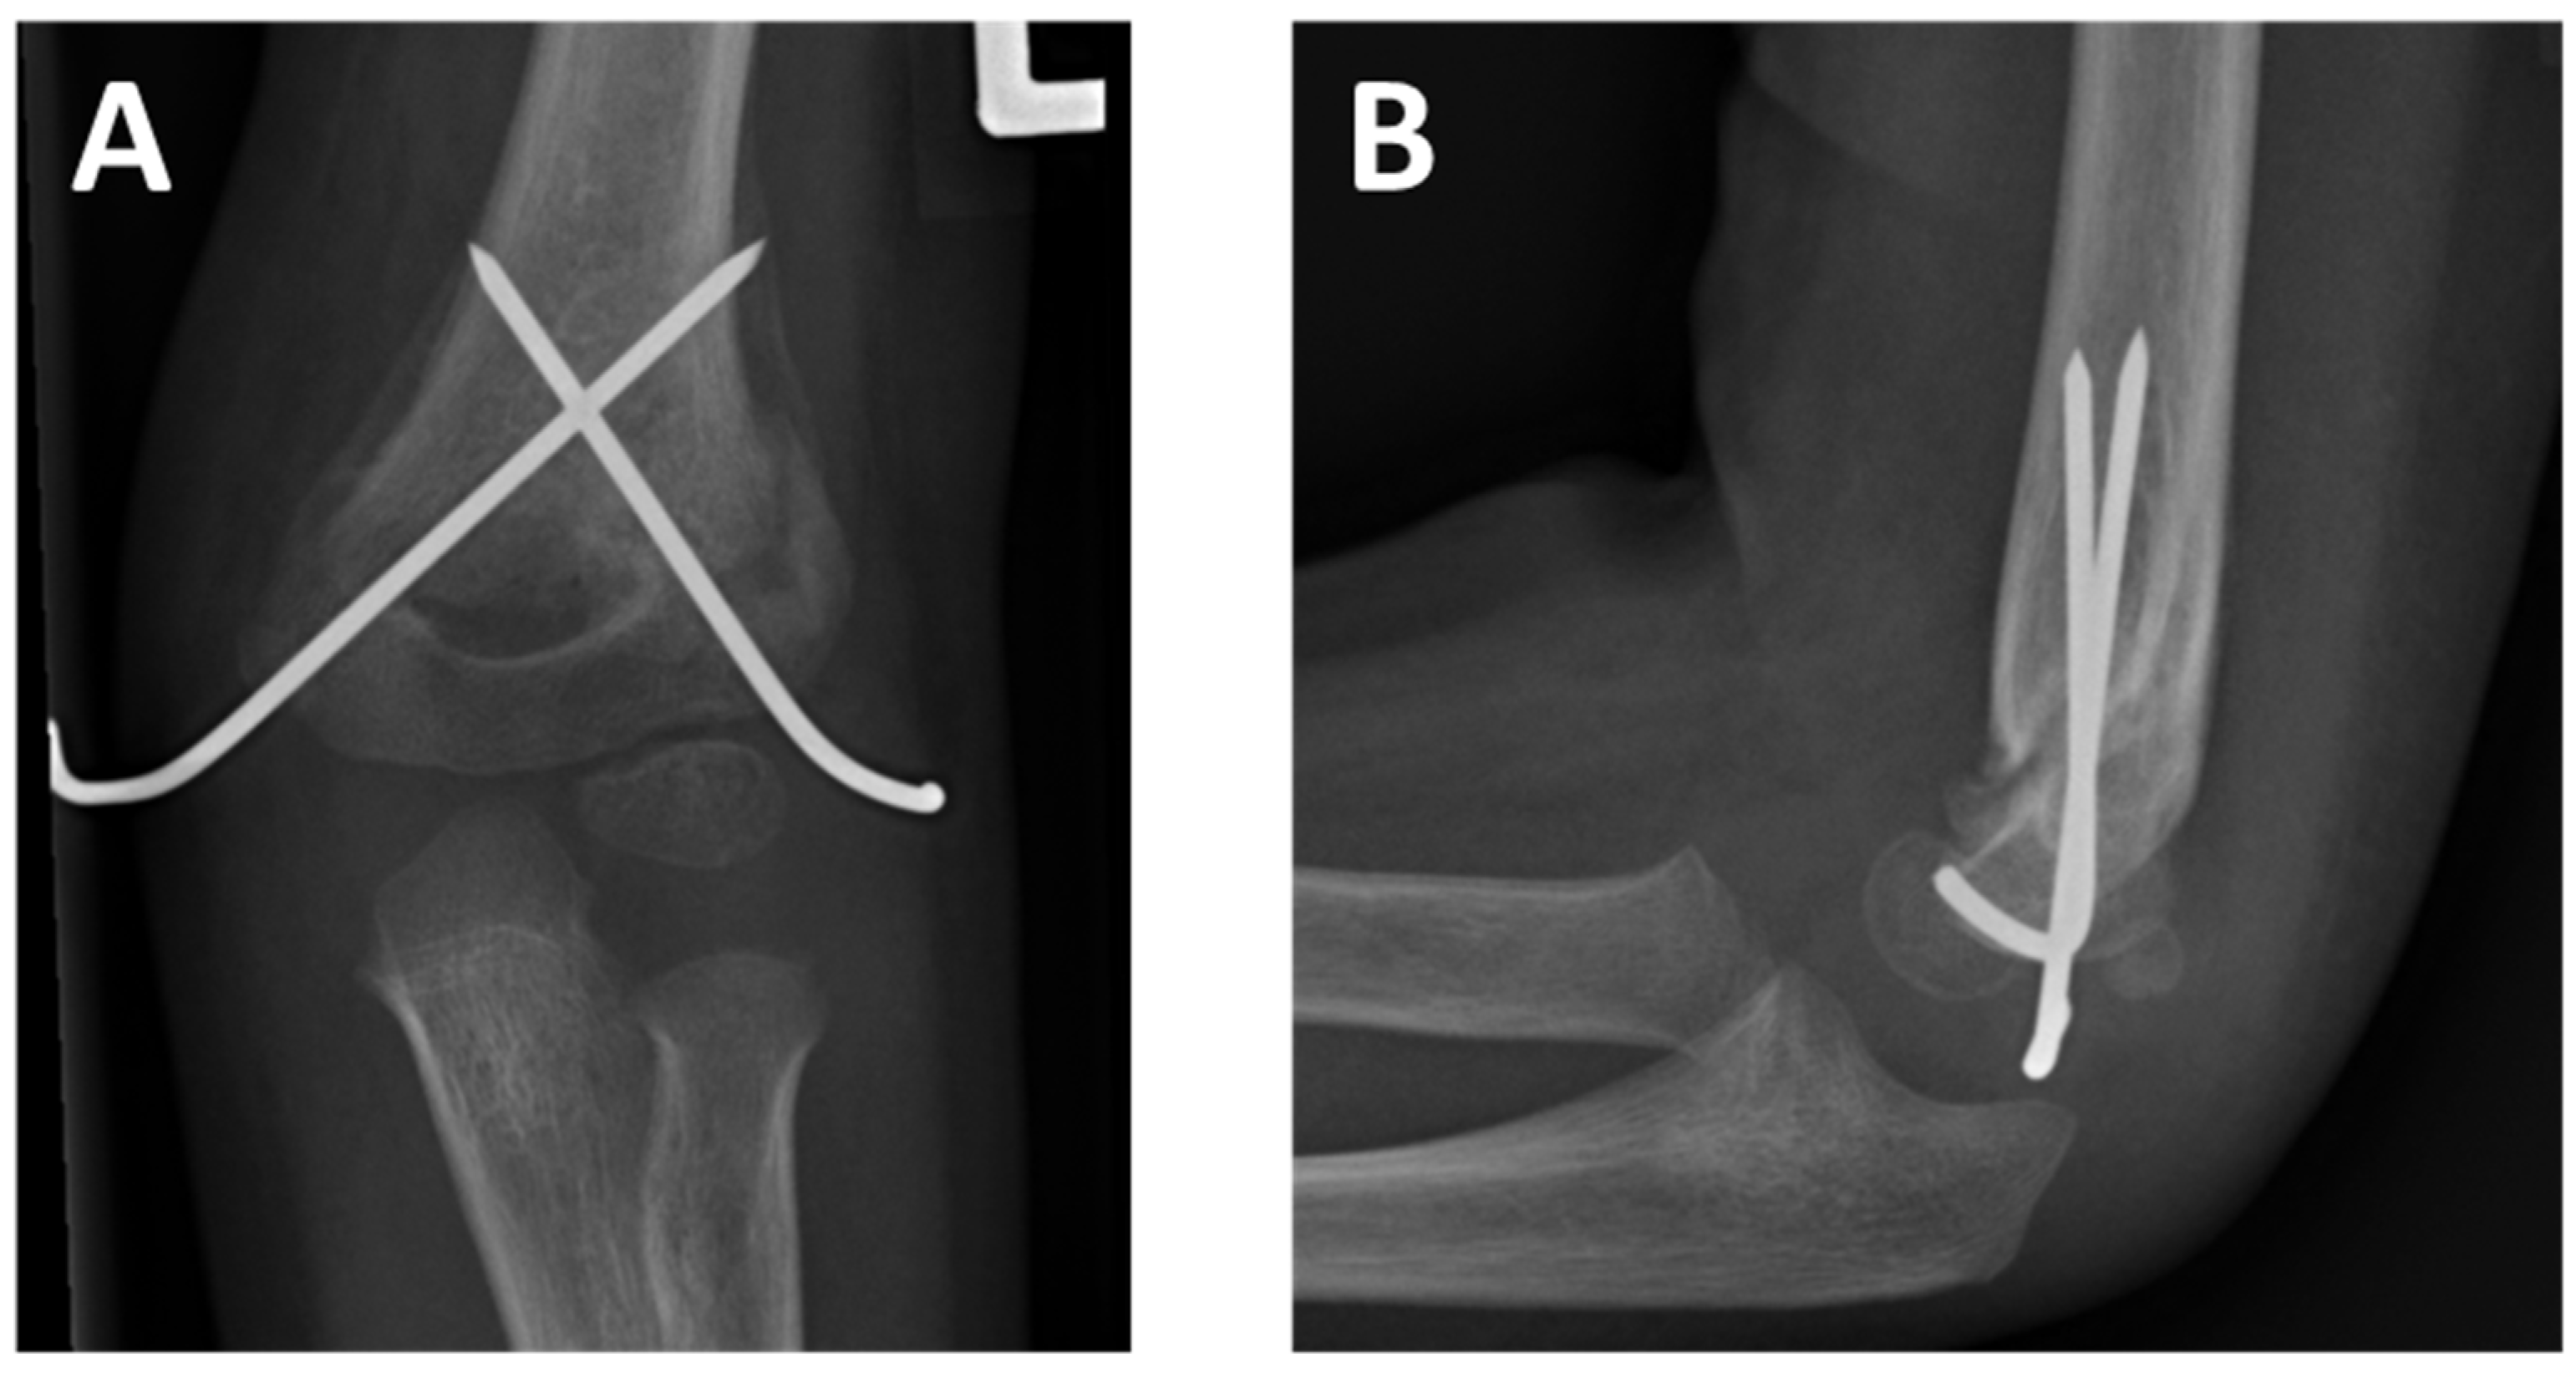

| Surgery | 14 (36%) PCP | 25 (64%) AN |

| Surgery | 3 (25%) PCP | 9 (75%) AN |